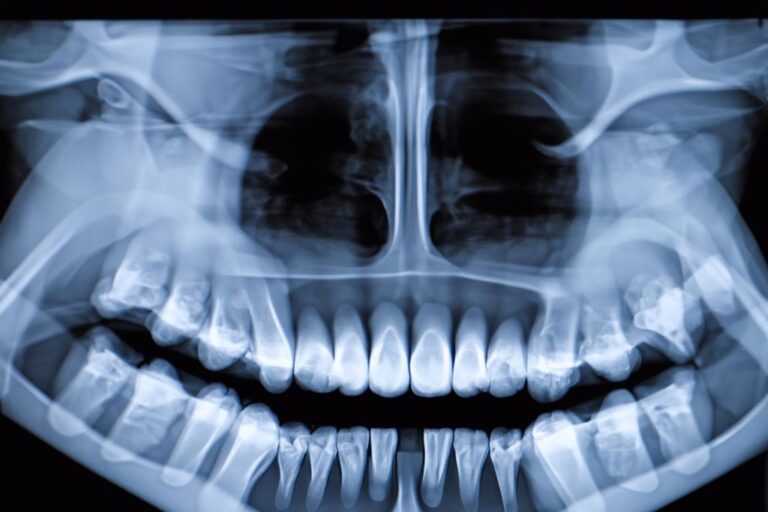

Η οδοντογενής ιγμορίτιδα είναι μια φλεγμονή του ιγμορείου, που προκαλείται από προβλήματα στα δόντια της άνω γνάθου. Το ιγμόρειο είναι μια κοιλότητα που βρίσκεται κοντά στη μύτη και πάνω από